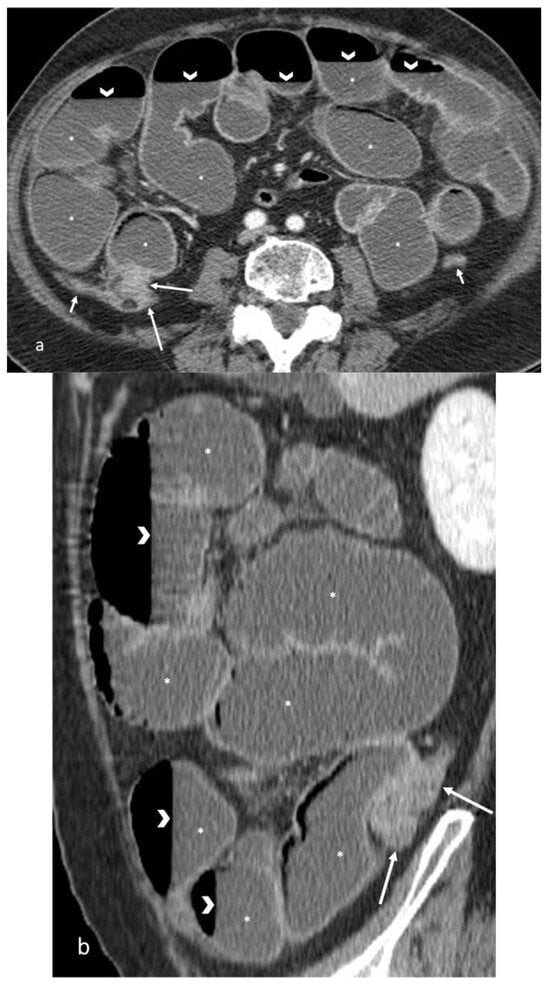

- A normal bowel loop caliber ranges between 2 and 2.5 cm. A bowel lumen is dilated when it has a maximum diameter greater than 2.5–3 cm. The dilation is mild when the upstream lumen is dilated up to 4 cm and severe when it is more than 4 cm (Figure 3) [24]. Pre-stenotic bowel dilatation should always be checked, as it is a sign related to bowel obstruction. Moderate to severe stenosis was determined via double-contrast imaging (conventional barium study) with a sufficient amount of injected air, and stenosis was defined as stenosis in which the lumen was less than one half that of neighboring healthy intestine [25].